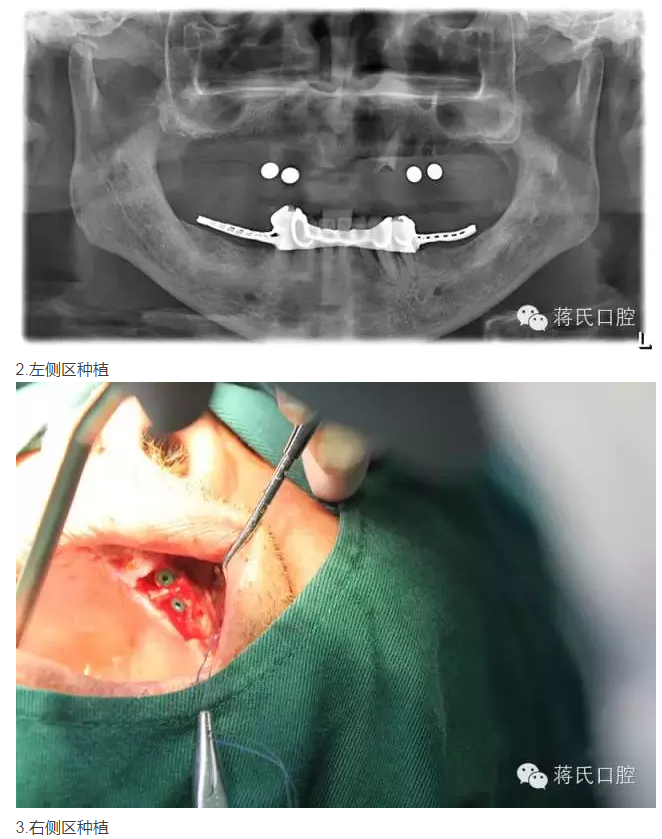

修復(fù)前全景片

3兩側(cè)四五區(qū)種植共4顆

4活動義齒雙重冠修復(fù)